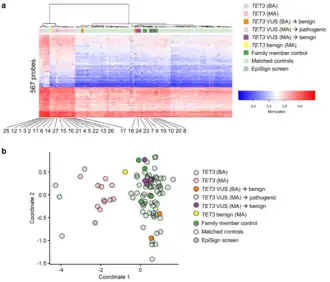

b. Multidimensional scaling was performed to stratify TET3 variants of uncertain significance (VUS) as either pathogenic or benign, based on their episignatures.[11]

Levy et al. (2021) discovered a distinct DNA methylation pattern or epigenetic signature (episignature)—demonstrating DNA hypermethylation—unique to pathogenic and likely pathogenic TET3 gene mutations. This episignature can be assessed through whole blood genome-wide DNA methylation analysis,[11] and may serve as a tool to confirm the pathogenicity of a TET3 variant of uncertain significance.[12]